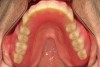

Fig 14. Digital scans were exported from the scanner and imported into dental laboratory software. An open-palate maxillary framework was designed, and virtual teeth were placed onto the scan. A tissue-surface design file was created, fitting the designed framework in the intaglio surface and pockets prepared for commercially available denture teeth.

Figure 14